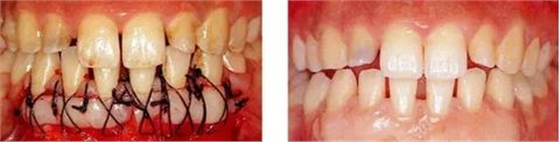

圖17-3(左) 為了獲得足夠的附著牙齦,在下頜前牙區(qū)進(jìn)行free gingival graft。讓游離齦移植片不要移動(dòng)地進(jìn)行緊密的縫合。

圖17-4(右)進(jìn)行free gingival graft 4年后的狀態(tài)。刷牙時(shí)無疼痛,牙齦也無退縮。